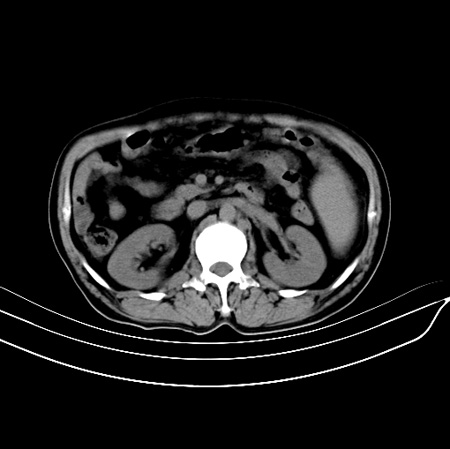

以下是引用江尾海头在2007-9-7 19:01:00的发言:[br]肝叶比例失调,肝边缘高低不平,尾状叶增大,肝裂增宽。肝右叶见较大密度减低影,边缘欠清。脾脏明显增大,胃底及奇静脉半奇静脉曲张。胆囊未见明显显示。 考虑:1、肝癌。2、肝硬化伴脾大静脉曲张。

以下是引用zhangxu5888在2007-9-7 22:31:00的发言:[br]1、肝硬化,食管 胃底及奇静脉半奇静脉曲张;2、脾脏肿大; 3、肝右叶的病灶呈锲性改变,内可见条片状钙化,边界清晰,密度明显低于周围正常肝组织,我觉得肝癌可能性不是很大, 同意楼上观点,有可能是栓塞,建议增强.